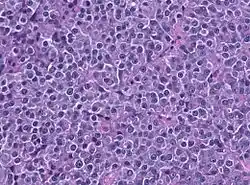

A prolactinoma is a tumor (adenoma) of the pituitary gland that produces the hormone prolactin. It is the most common type of functioning pituitary tumor.[1] Symptoms of prolactinoma are due to abnormally high levels of prolactin in the blood (hyperprolactinemia), or due to pressure of the tumor on surrounding brain tissue and/or the optic nerves. Based on its size, a prolactinoma may be classified as a microprolactinoma (<10mm diameter) or a macroprolactinoma (>10mm diameter).

Though most pituitary tumors are sporadic, some genetic syndromes include increased risk for pituitary adenomas including Multiple endocrine neoplasia type 1 (caused by a mutation in the MEN1 gene), multiple endocrine neoplasia type 4 (MEN4 gene), Carney complex, and Familial isolated pituitary adenoma (FIPA).[2] Despite their frequent association with genetic syndromes that cause multiple cancers in affected body tissues, the large majority of prolactinomas are monoclonal in origin (originating from a single cell developing a random mutation), even in cases where the tumor begins producing multiple distinct hormones aside from prolactin.[7][2]